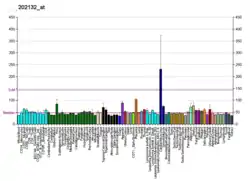

Cancers

WWTR1 (TAZ) is implicated a wide variety of cancers including melanoma, head and neck squamous cell carcinoma, breast cancer, non-small cell lung cancer, and others due to its high gene and histological expression, as well as correlation with increased metastasis and poorer survival in animal studies and patient data.[9] Along with the structurally similar co-regulator YAP, many studies have described their role in promoting oncogenesis, altering neoplastic metabolism, and generating resistance to therapeutic intervention.[8][9][32][33] In particular, TAZ overexpression conferred resistance to cisplatin chemotherapy as well as immunotherapy treatment with a PD-1 antibody.[32]